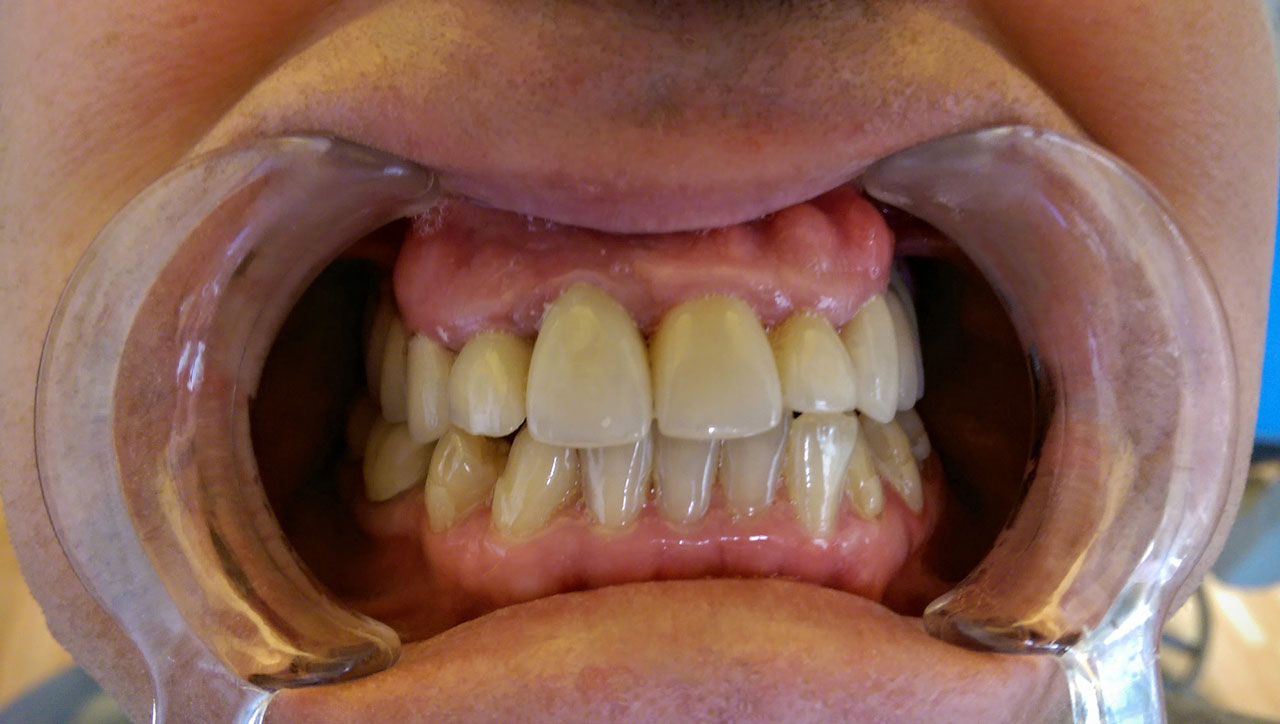

Teljes szájüregi rehabilitáció két lépésben

Ismét egy teljes szájüregi rehabilitáció két lépésben. Először az alsó fogak lettek kihúzva és azonnal implantálva, híddal ellátva, majd később a felső. IHDE svájci azonnal terhelhető implantátumok és cirkónium hidak. Dr. Kelemen Péter és a Symbion Fogtechnika közös munkája.